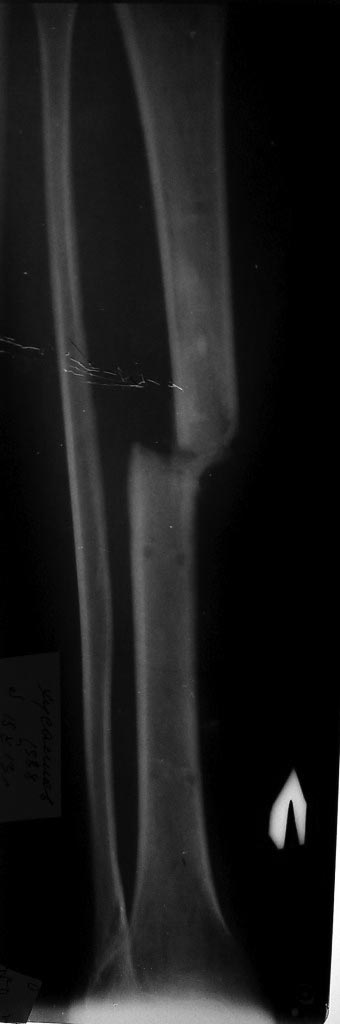

Уважаемые коллеги! Помогите определиться с тактикой лечения у молодого

пациента.

Молодой парень, 25лет. Травму получил в ноябре 2012 года, ДТП.Оперирован

АВФ на голень с этой стороны, наложена гипсовая повязка коксит на 3

рентгенапаратом. Как быть с ложным суставом голени?

1. БИОС голени- оптимальный вариант,но при отсутствии желаемого сгибания

в коленном суставе сможем ли мы сделать( Наш опыт - всего 30 операций по

БИОСу)

2ЧКДО по Илизарову( после АВФ)